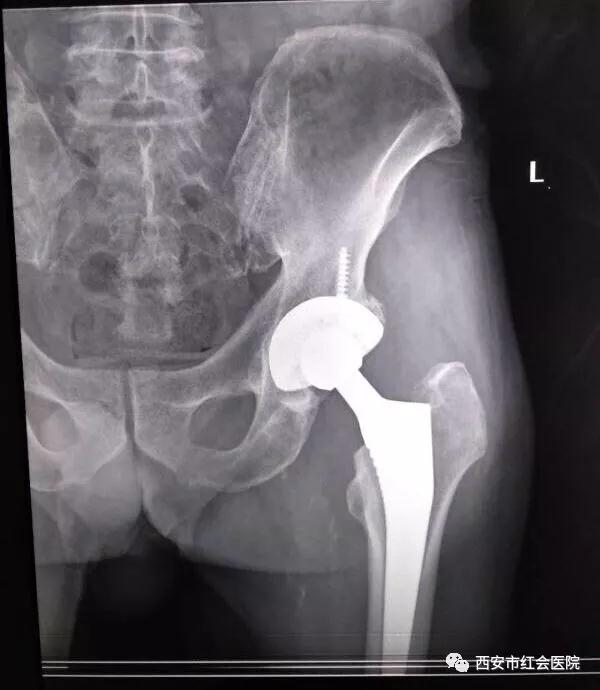

据了解,4床患者系70多岁老人,1个月前在西安市红会医院关节病医院行手术治疗,出院后定期行康复功能锻炼。

6号晚上11点多,老人在家不慎摔倒,将术后的髋关节受伤脱位,紧急来到红会阎良院区救治。

接诊的张亮副主任和成德亮主治医生,立即给予拍片、行手法复位及固定等治疗。